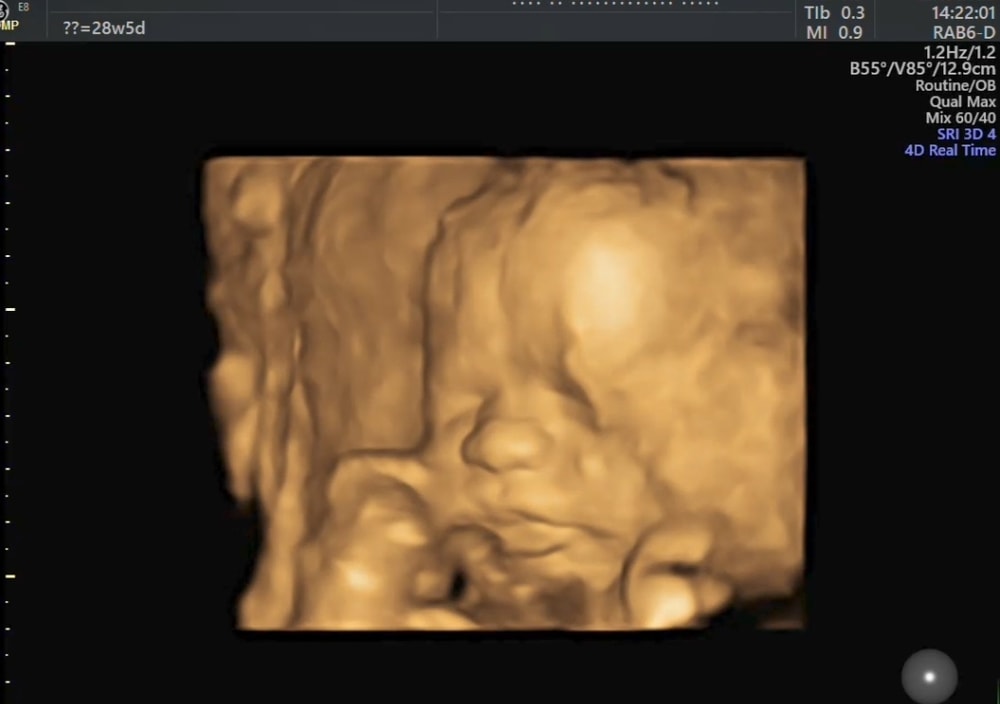

28+5 🩵

И улыбался, и пальчик пососал, и язык показал, а лицо не очень хотел показывать. Руками и ногами закрывался постоянно.